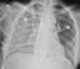

Strongyloides stercoralis is a human pathogenic parasitic roundworm causing the disease strongyloidiasis. Its common name in the US is threadworm. [Source: Wikipedia ]